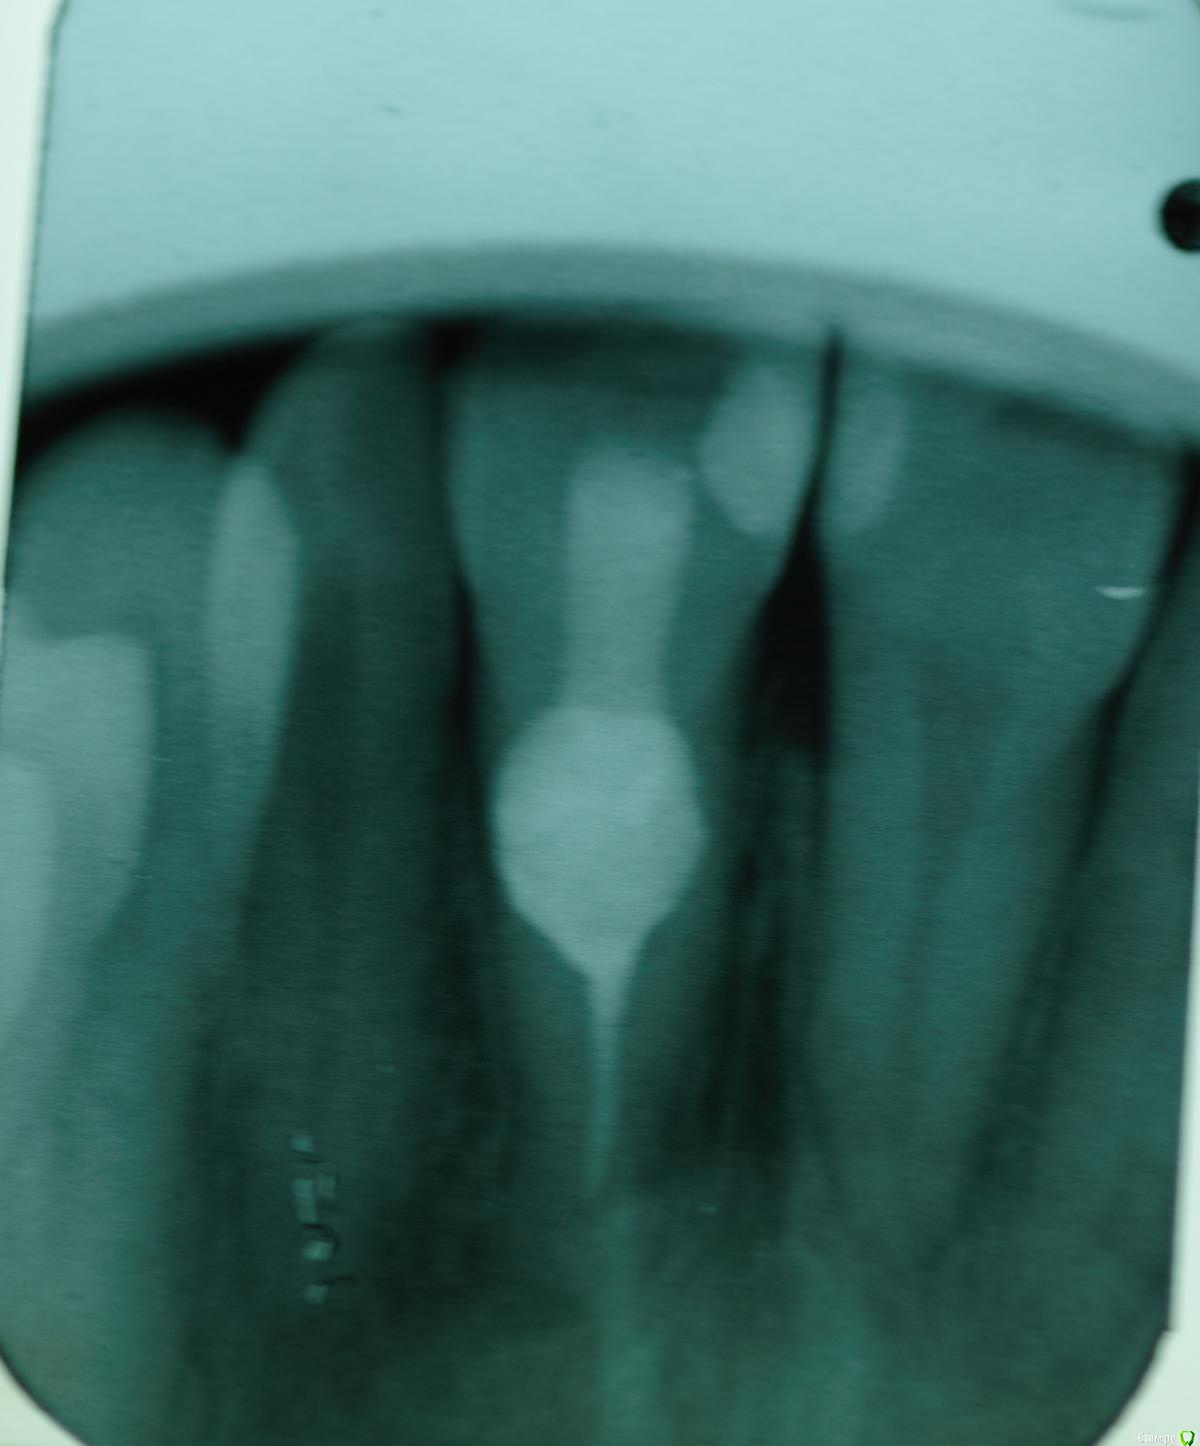

skeettrap Опубликовано 5 апреля, 2016 Поделиться Опубликовано 5 апреля, 2016 Случай двухлетней давности. Коллега привела подругу. Жалобы только на свищ в области данного зуба с грануляциями. Делали на "сколько простоит". Сегодня попросил администратора вызвать пациентку для контроля. Если придет, то будет продолжение. 1 Ссылка на комментарий

skeettrap Опубликовано 5 апреля, 2016 Автор Поделиться Опубликовано 5 апреля, 2016 (изменено) Латеральная конденсация. В очаге резорбции - МТА. Изменено 5 апреля, 2016 пользователем skeettrap Ссылка на комментарий

skeettrap Опубликовано 7 июня, 2016 Автор Поделиться Опубликовано 7 июня, 2016 (изменено) Наконец пациентка дошла. Пока все нормально и свищ не появлялся больше. Зуб 21. Изменено 7 июня, 2016 пользователем skeettrap 3 Ссылка на комментарий

vse32 Опубликовано 7 июня, 2016 Поделиться Опубликовано 7 июня, 2016 У внутренних резорбций самый предсказуемый прогноз. Главное вычистить всю органику из канала и зоны резорбции. Тогда процесс остановится.Минус, если резорбция перфарирующая. Но и здесь все зависит от площади перфорирования и аккуратности. Самое сложное в таких случаях - запломбировать канал за зоной резорбции.Поздравляю. Ссылка на комментарий